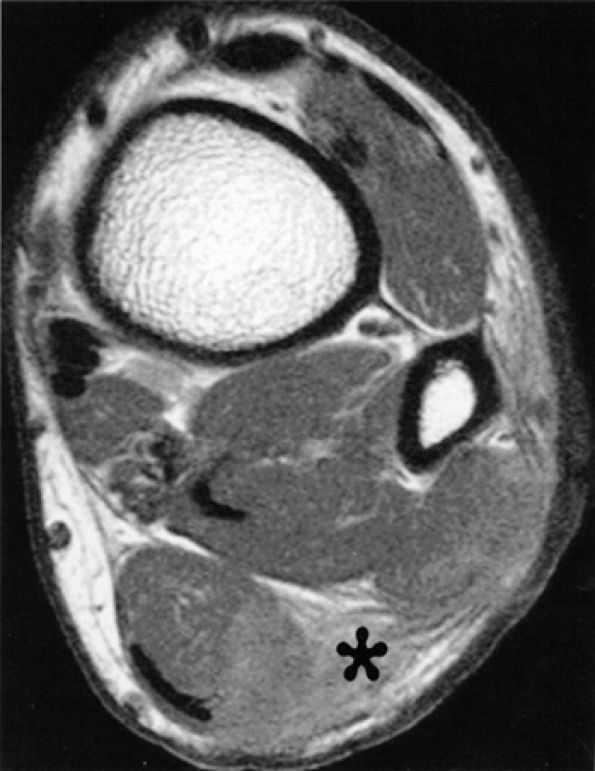

An oval or dumbbell-shaped mass of intermediate to low signal on both T1- and T2-weighted MR images located in the intermetatarsal space. The mass frequently extends into the plantar subcutaneous fat and may be associated with intermetatarsal bursitis (Fig. 6.59).

The low signal of the lesion reflects its predominant histologic composition of dense fibrous tissue.

T1-weighted images are optimal for detecting the neuroma since they provide good contrast between the lesion and the adjacent fat.

T2-weighted images serve to confirm the diagnosis as well as to exclude other diagnostic possibilities, such as true neuromas, intermetatarsal bursitis, ganglion cysts, and synovial cysts.178,193,194,195

The lesion is centered in the neurovascular bundle, within the intermetatarsal space and on the plantar side of the transverse metatarsal ligament.

The lesion is well demarcated.

The signal intensity of the lesion is similar to that of skeletal muscle on TI-weighted images and less than that of fat on T2-weighted images (see Fig. 6.59).

FIGURE 6.59 ● Third intermetatarsal Morton's neuroma. Dumbbell mass (arrows) of intermediate to low signal on both T1-weighted (A) and T2-weighted (B) images extends from the intermetatarsal space to the plantar aspect of the foot. (C) The mass enhances after gadolinium administration.